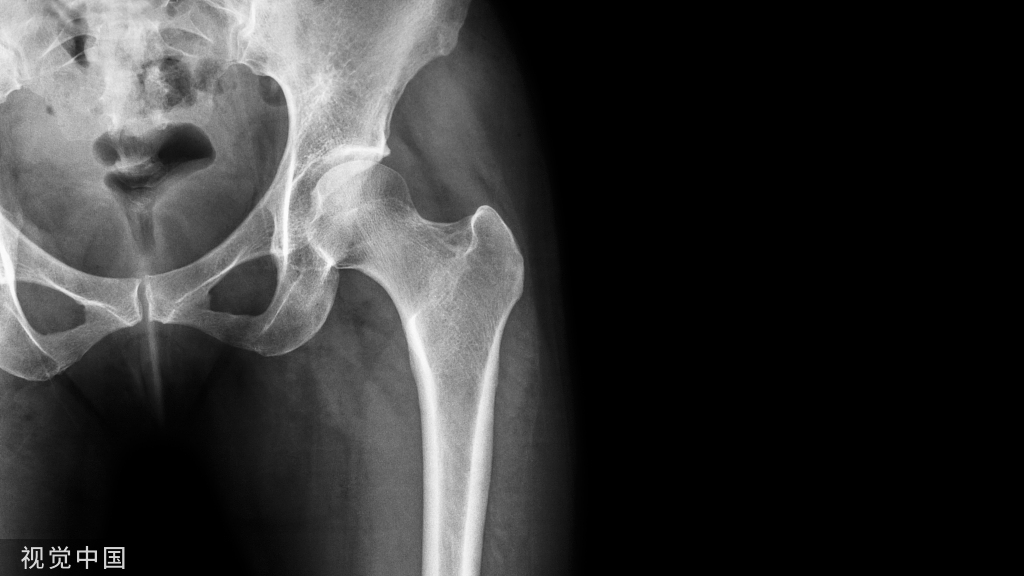

说到复位的细节,就要了解肱骨远端的解剖

1.解剖中比较重要的就是柱的概念,分为外侧柱和内侧柱,一个重要的滑车结构包含了300度的关节面,在外侧有一个肱骨小头的结构,然后一个冠突窝的结构

2.其中有几个重要的角度,4-8度的轻微外翻角,30度前方的前倾角

肱骨的内外侧柱和滑车构成了一个三角形稳定结构,手术复位的时候一定要完成稳定三角结构的恢复。

肱骨远端的三个神经也需要注意哦,尤其是后入路的时候,有时需要对桡神经和尺神经都进行显露。